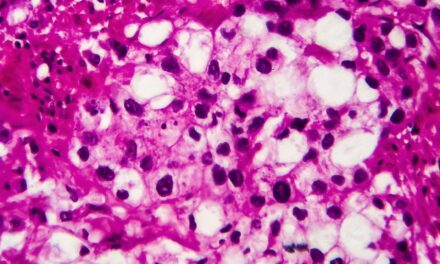

A University of Warwick study finds AI cancer detection models may rely on statistical correlations rather than true biomarker signals, raising concerns about reliability in clinical pathology applications.

AI models used to analyze pathology samples can infer patient demographic information, leading to biased cancer diagnoses.